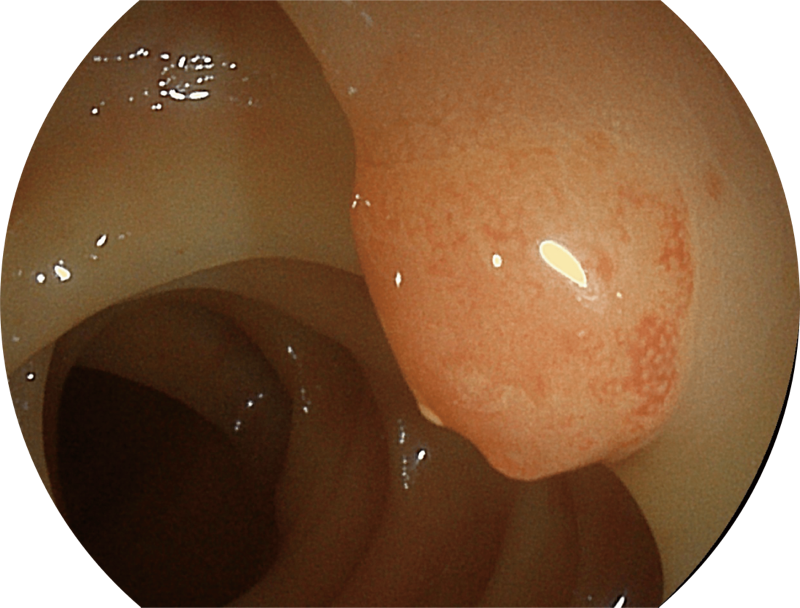

聚谱成像

(Spectral Focused lmaging, SFI)

能够凸显黏膜浅层和中层血管轮廓,适用于中、远景观察下的病灶识别和早癌筛查。